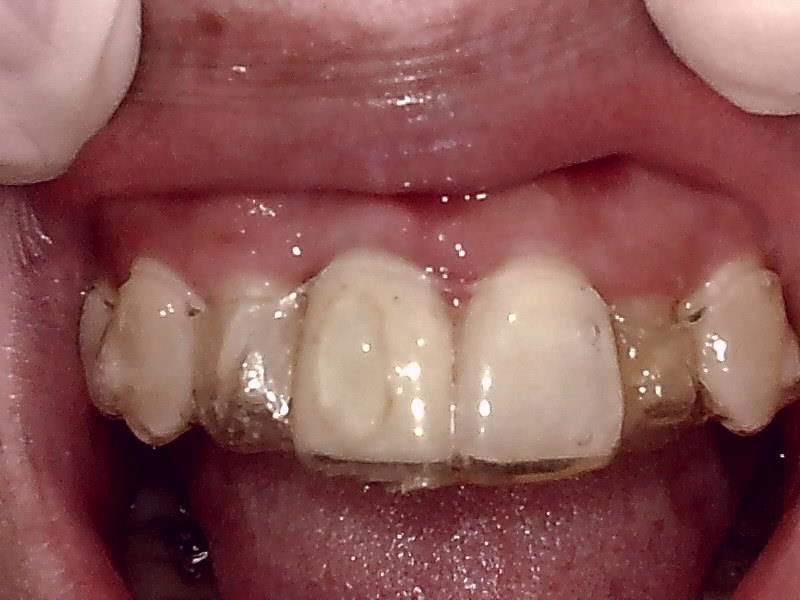

インビザライン矯正中よりアライナー装着している。

術後、インビザライン矯正中よりアライナー装着中